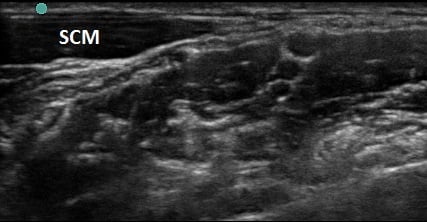

Figure 2a. Transverse view through the interscalene space

Figure 2b. With labels

- Identify the middle scalene muscle posterior to the anterior scalene muscle.

- The interscalene space is between these 2 scalene muscles and contains the brachial plexus

- Visualize the brachial plexus here as a stack of circles with hypoechoic centers

- The plexus will look more echogenic, bundled and honeycombed in the caudal interscalene space